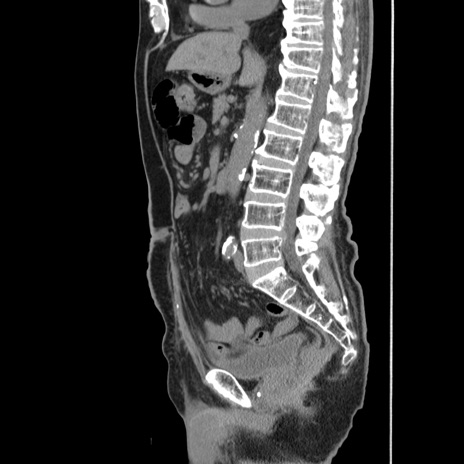

症例24(矢状断像)

【症例】80歳代男性

【主訴】左側腹部痛、嘔吐

【現病歴】本日早朝より左腹部に痛みあり。昼頃嘔吐認めたため、救急要請。

【既往歴】直腸癌(Mile手術)、胆摘

【身体所見】意識清明、BT 35.9℃、BP 221/93mmHg、SpO2 97%(RA) 、腹部:左ストーマ周囲に限局性の腹部膨隆あり。 膨隆部自発痛・圧痛あり・軟。

【データ】WBC 7700、CRP 0.09